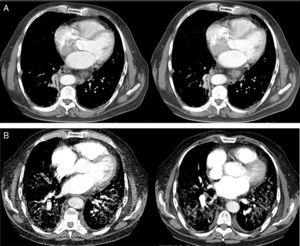

The computed tomography results are shown in Fig. 1, while the bronchoscopy study only showed supraglottal polypoidal lesions. Bronchial aspiration cytology was negative for neoplastic cells.

Evolution of the pulmonary involvement shown by axial computed tomography (ACT). (A) ACT of the thorax at diagnosis revealed the presence of discrete interstitial infiltrates in ground glass opacity in the bases and periphery of the lungs, and to a lesser degree, in the mid-fields, with multiple mediastinal lymphatic ganglia of less than 17mm and segmental atelectasis of the lower right lobe. (B) At 3 months the angio ACT showed no images of pulmonary thromboembolism, although extensive bilateral involvement of the lungs was observed, with interstitial infiltrates with ground glass opacity and interlobular septal thickening, as well as areas of fibrosis, while the anterior pulmonary fields were less involved.